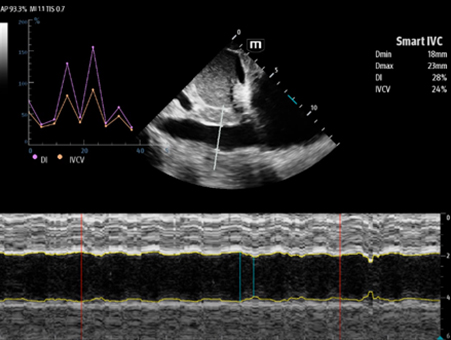

Mindray's Emergency Ultrasound Solutions address clinical challenges through a systemic approach. Those solutions cover the entire emergency care process from pre-hospital rescue and ambulance transport to ER treatment and in-hospital transfer. The versatility of Mindray Ultrasound shaping from Tablet system, Laptop-based system to Handheld Ultrasound system brings up the power of Ultrasound at the point of care. Clinical oriented smart features and protocols assist decisions with confidence.